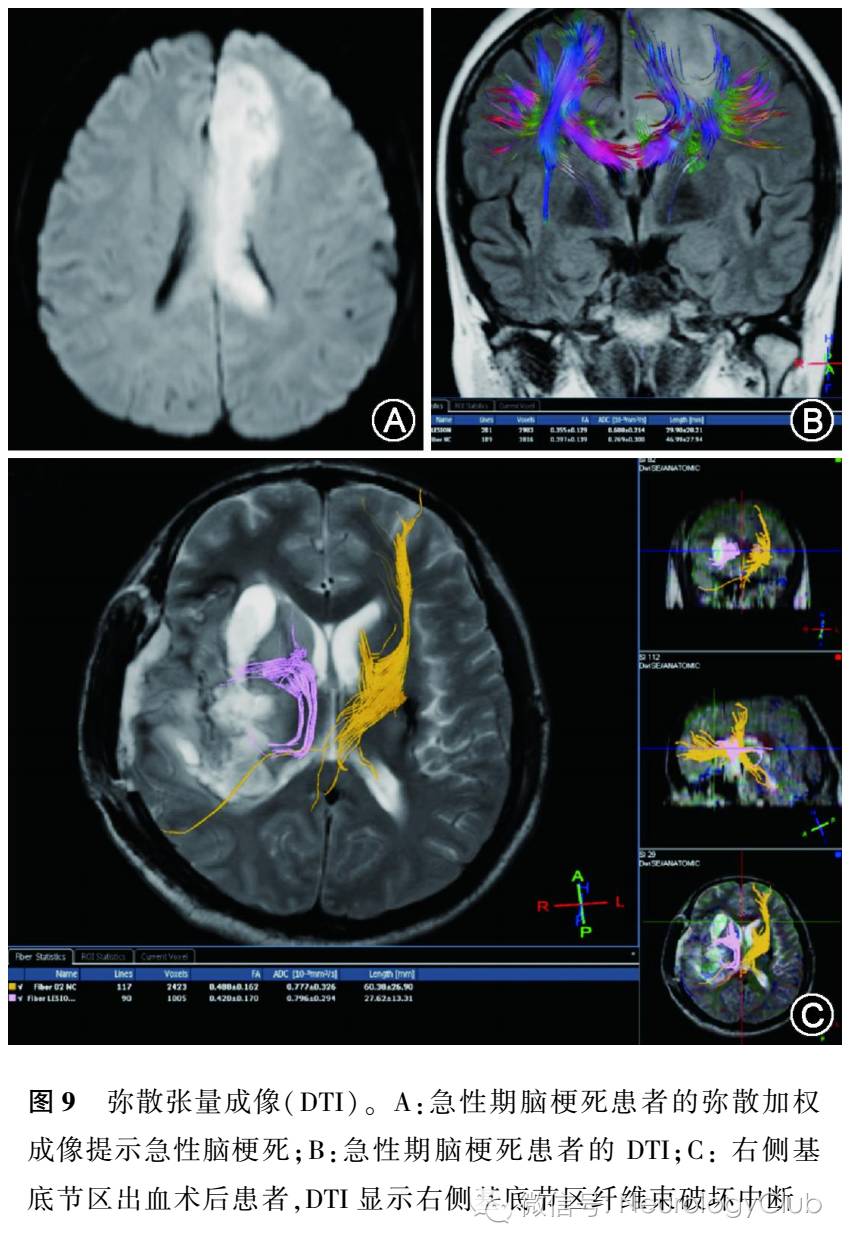

DTI是MR扩散加权成像基础上发展起来的一种新的成像方法,它通过在多个方向上施加弥散敏感梯度来测量水分子弥散的程度和方向性,比DWI的表观扩散系数(ADC)值更能准确并全面地反映弥散信息。DTI定量分析最常用的参数,为各向异性分数、ADC、平均弥散率、弥散张量纤维束成像。DTI同普通DWI相比,不仅可以准确评价不同时期脑梗死时脑灰、白质内水分子弥散各向异性改变的特点,并且可以经过重建的特征矢量图,显示出慢性期脑梗死病灶远端神经纤维束走向的改变及其完整性(图9),从而为神经轴突的完整性评价提供信息。研究证实发病24h内的缺血性脑梗死中,病灶的扩散各向异性显著降低,可以根据降低程度来区别梗死核心区及缺血半暗带。DTI不仅可以准确评价不同时期脑梗死水分子扩散各向异性改变的特点,还能通过纤维束示踪成像显示脑梗死病灶远端神经纤维束走向改变及其完整性,从而能评价脑梗死患者预后。Thomalla等对发病2-16d内的亚急性期的轻、中度幕上缺血性卒中患者行DTI检查,认为DTI在变性程度的判断及患者运动功能转归的预测上具有一定的优势。